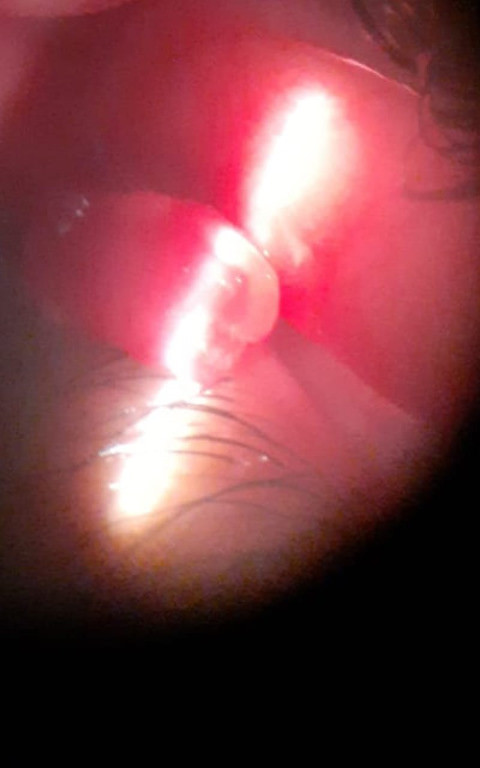

Casos Clínicos

Envíado por Dr. José Alfredo Martínez